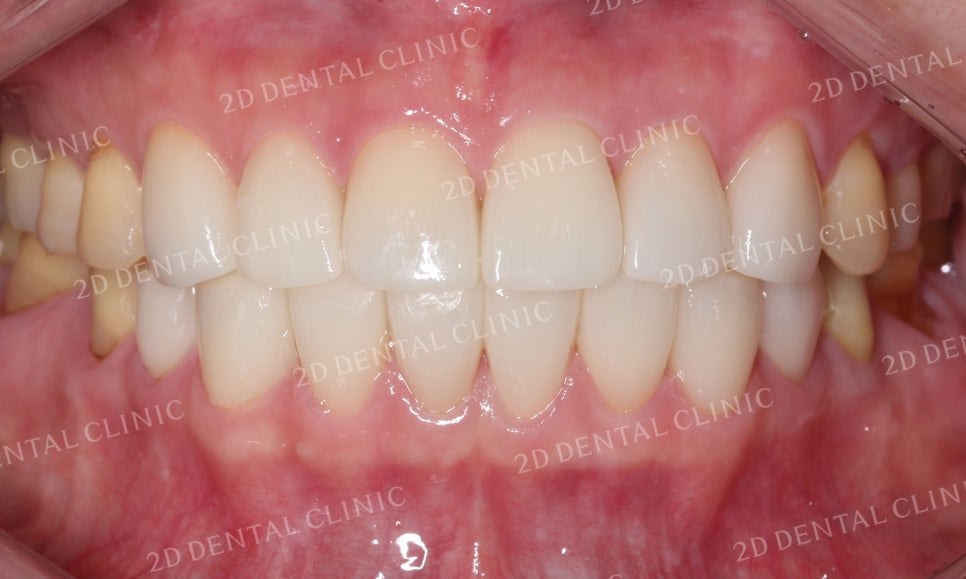

블링스 시술 전후 전치부의 사진입니다.

잇몸의 퇴축으로 치아 사이에 빈틈이 보이던

시술 전과 달리 시술 후 치아가 예쁘게 자리잡힌 모습이네요~

안모의 자세한 사진에서도

비어있던 빈 틈이 완벽하게 채워진 모습입니다.

블랙트라이앵글이 보이던 하악도

잘 채워진 모습이네요!